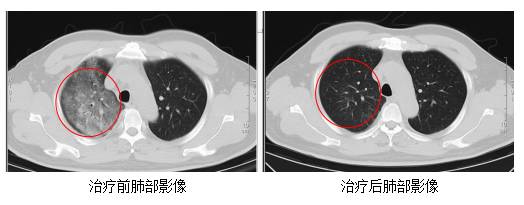

江蘇最近確診一宗罕有傳染病「Q熱」(寇熱)個案,一名顧姓男子從非洲回國10天後,出現了發熱、咳嗽、乏力、四肢肌肉酸痛以胸悶等徵狀,胸部電腦掃瞄顯示他雙肺出現大面積炎症病變,最終確診為「貝納柯克斯體」感染引起的「Q熱」。情況如當年爆發新冠病毒相似,國內人士擔心會出現大規模爆發。這種罕見傳染病,感染初期出現的病癥與重感冒相似,例如發高燒、持續發燒達 15 天、甚至引起心內膜炎、肝炎、脊髓炎、腦炎等嚴重疾病。接觸受感染的動物是主要傳播途徑,近年流行北上深圳買餸,接觸活家禽時要加倍小心,有飼養寵物的人士也要加倍留心!不過「Q熱」屬罕有傳染病,大家北上玩或買餸時也不用過份擔心,做好個人衛生習慣及照顧好寵物就可以了。